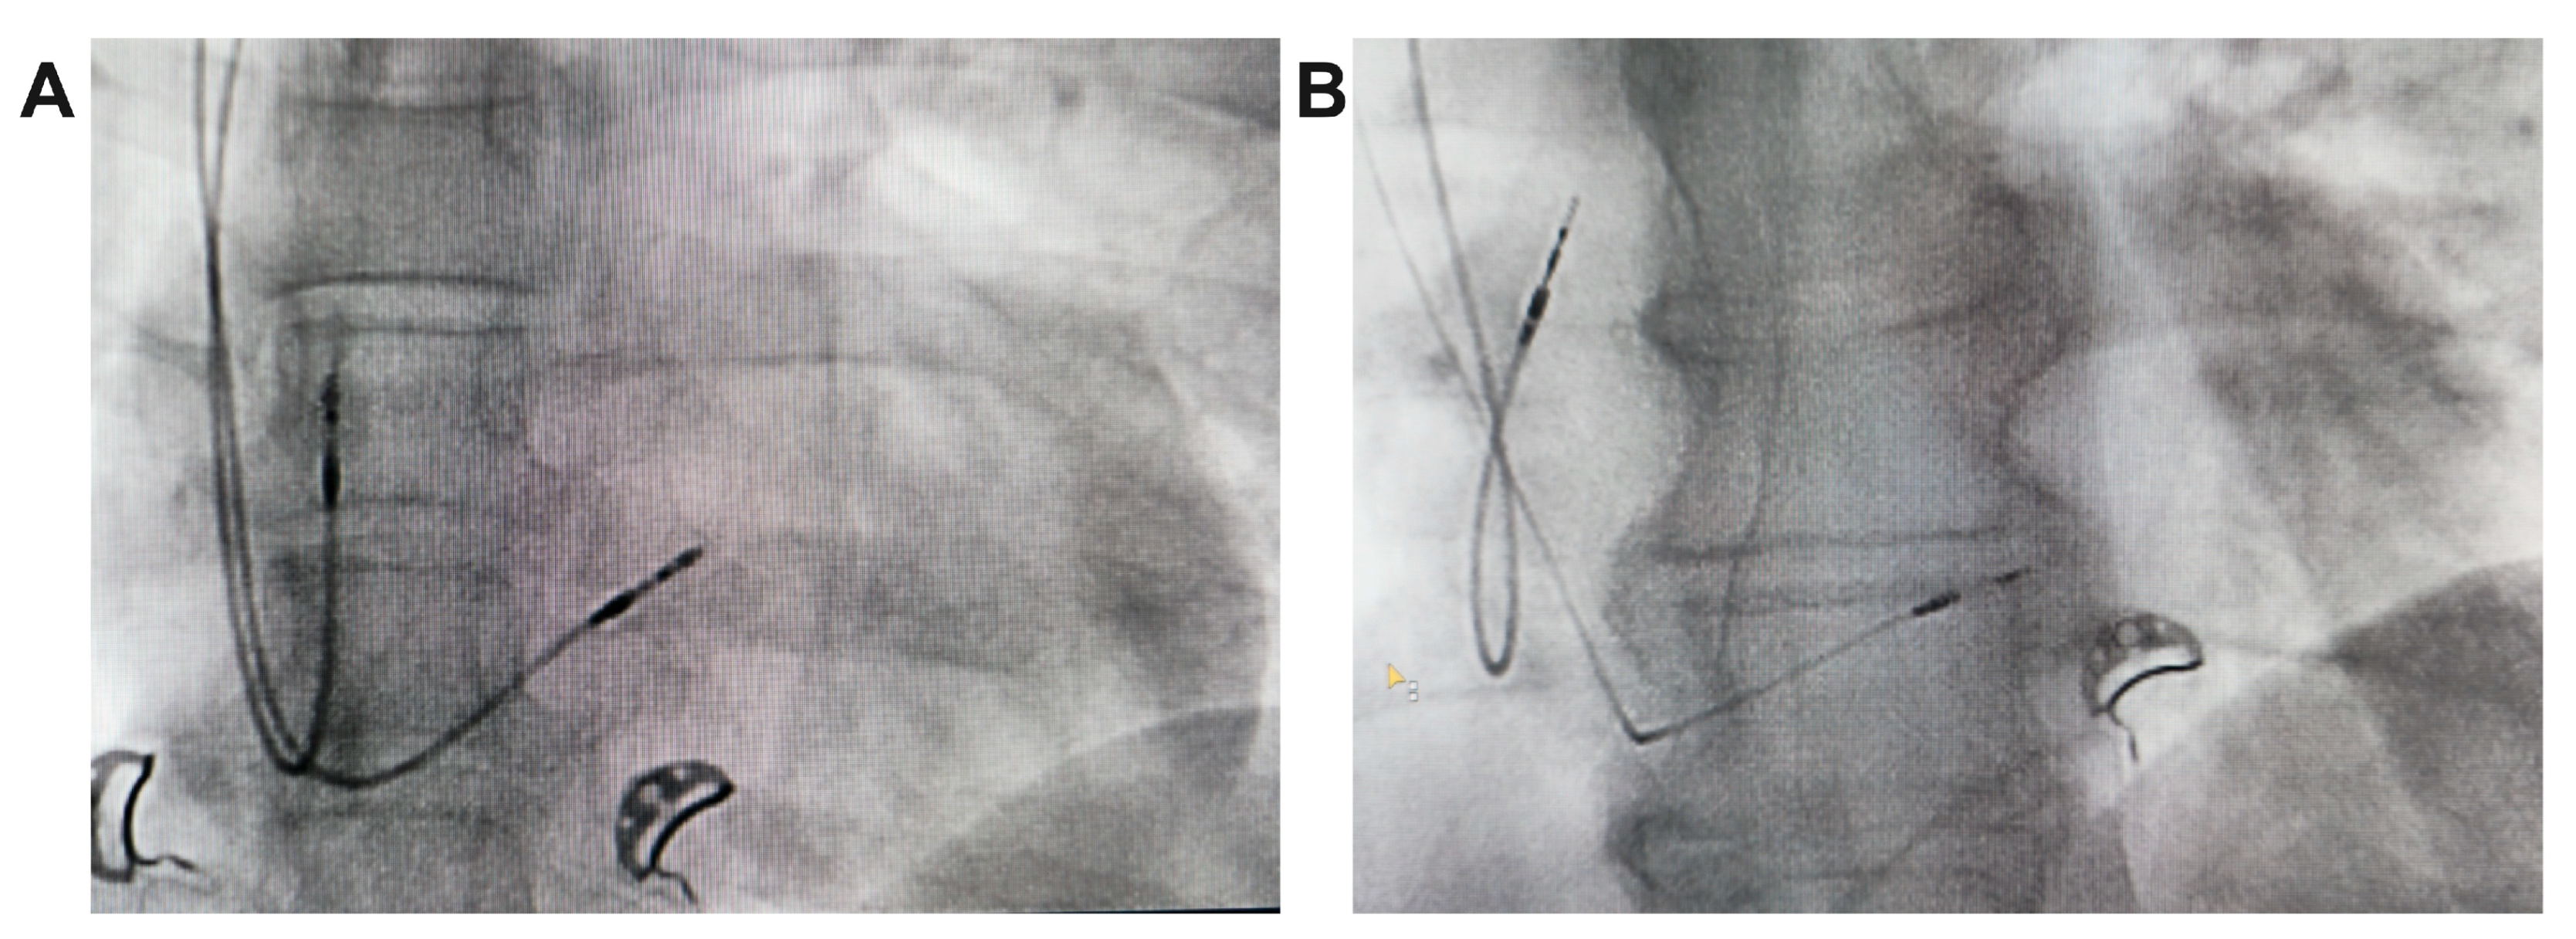

Implant Procedure